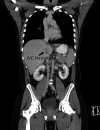

A young adult male was referred for a second opinion of deranged liver biochemistry. He initially presented two years prior with abdominal pain, lethargy and fevers due to a segment two pyogenic liver abscess. He received empirical antibiotic therapy to resolution. Computed tomography for abscess follow-up revealed an intrahepatic inferior vena cava thrombus. He was anti-coagulated with warfarin. He was lupus anticoagulant positive and had a highly positive beta-2 glycoprotein antibody on serial measurement and was diagnosed with anti-phospholipid syndrome. On current review, the patient had no clinical stigmata of chronic liver disease. There were dilated veins on the supraumbilical abdominal and chest walls. There was mild hepatomegaly but no splenomegaly. Laboratory investigations revealed mildly cholestatic liver function tests with hyperbilirubinaemia (40μmol/L) but no liver synthetic dysfunction. Serological screening did not reveal any cause of chronic liver disease. The patient underwent multiphase abdominal CT and formal hepatic venography. What is the diagnosis and describe the hepatic venous outflow?